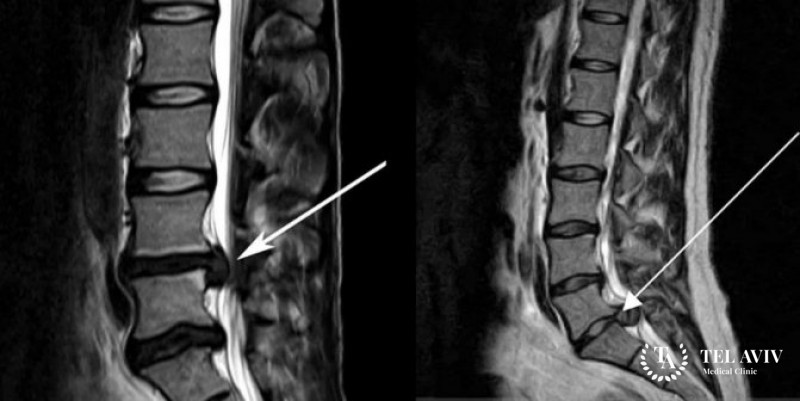

- магнитно-резонансная томография;